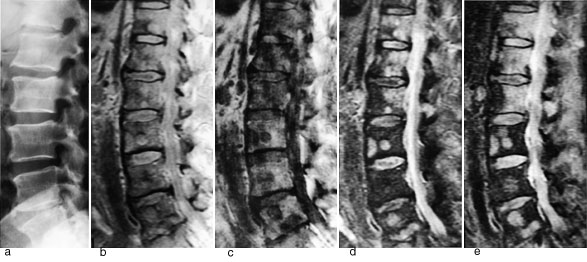

Figur 1 illustrerer det potensialet MR har til å påvise skjelettmetastaser. Protontetthetsbildet viser metastaser klart tydeligere enn det elektrontetthetsbaserte konvensjonelle røntgenbildet. Det T1-vektede bildet viser multiple metastaser med lavt signal, det T2-vektede bildet fremstiller metastasene med høyt signal. STIR (short inversion time inversion recovery)-bildet fremstiller også metastasene med høyt signal. På denne sekvensen summeres effekten av en lang T1 og en lang T2 (typisk for tumor), samtidig med at signalet fra fett er undertrykt. Dette gir sekvensen meget høy sensitivitet.

Ved truende og manifeste tverrsnittslesjoner hos kreftpasienter vil årsaken oftest være skjelettmetastaser med omgivende intraspinal, ekstradural bløtdelstumor som komprimerer medulla. Minst 20 % av pasientene vil ha medullakompresjon på mer enn ett sted (6). Hele columna bør undersøkes. MR viser både metastasene og medullakompresjonen, og MR-undersøkelse er den beste metoden til å utrede disse pasientene. Sagittale T1-sekvenser og STIR- eller T2-sekvenser gir god oversikt over medulla (fig 2), og kan eventuelt suppleres med aksiale snitt svarende til medullakompresjonen. I en artikkel i Tidsskriftet har Brenne og medarbeidere gitt en utførlig omtale av medullakompresjon ved metastatisk kreftsykdom (7). Vi slutter oss til det syn at utredningen bør skje raskt, ved hjelp av MR. Det er viktig å være oppmerksom på at de aller fleste pasienter med medullakompresjon har hatt utstrålende radikulære smerter i nivå for kompresjonen i forkant av de nevrologiske utfall.

Ved osteogent sarkom og Ewings sarkom kan MR med snittplan i knokkelens lengdeakse nøyaktig fastslå øvre og nedre grense for tumorutbredelse i beinmargen (fig 5), påvise metastaser innenfor samme margrom og innvekst i ledd. Dette er forhold som har stor betydning for omfanget av kirurgiske inngrep. Som regel har tumor på diagnosetidspunktet brutt gjennom knokkelen og gitt opphav til en ekstraossøs komponent. Med snittplan perpendikulært på knokkelen kan MR vise om tumor affiserer kar og nerver, og hvilke muskler den ligger an mot eller infiltrerer. MR kan styre biopsitakingen til de områder av tumor hvor det er størst sannsynlighet for å finne representativt vev.